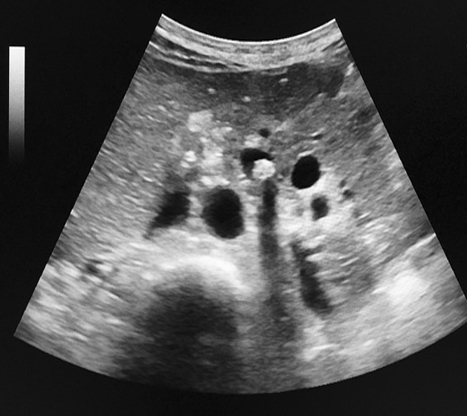

Meme cas en coupe

transversal a travers le calcul Image du calcul

hyperechogene se voyait tres nette avec cone

de l'ombre de acoustique posterieure . |